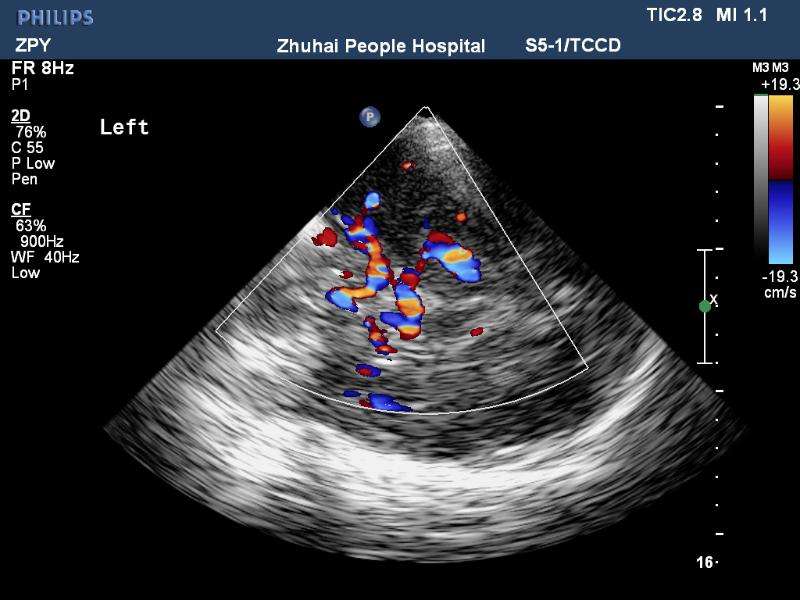

經(jīng)顱彩色編碼雙功能超聲(transcranial color-coded duplex sonography

TCCD)是一種非侵入性發(fā)現(xiàn)顱內(nèi)動脈異常血流動力學(xué)狀態(tài)的可靠方式。TCCD成像原理是在TCD基礎(chǔ)上增加了二維灰階實時顯像以及彩色編碼雙功能超聲成像,在二維顯示顱內(nèi)解剖結(jié)構(gòu)的同時,同時對運動紅細(xì)胞產(chǎn)生的多普勒頻移進(jìn)行彩色編碼。應(yīng)用TCCD檢測時可以通過在感興趣區(qū)內(nèi)多點取樣,得出取樣容積內(nèi)多普勒頻移曲線,通過雙側(cè)對比、左右對比以及前后對比,綜合評價缺血性腦血管病受檢者Willis環(huán)的血流動力學(xué)變化。